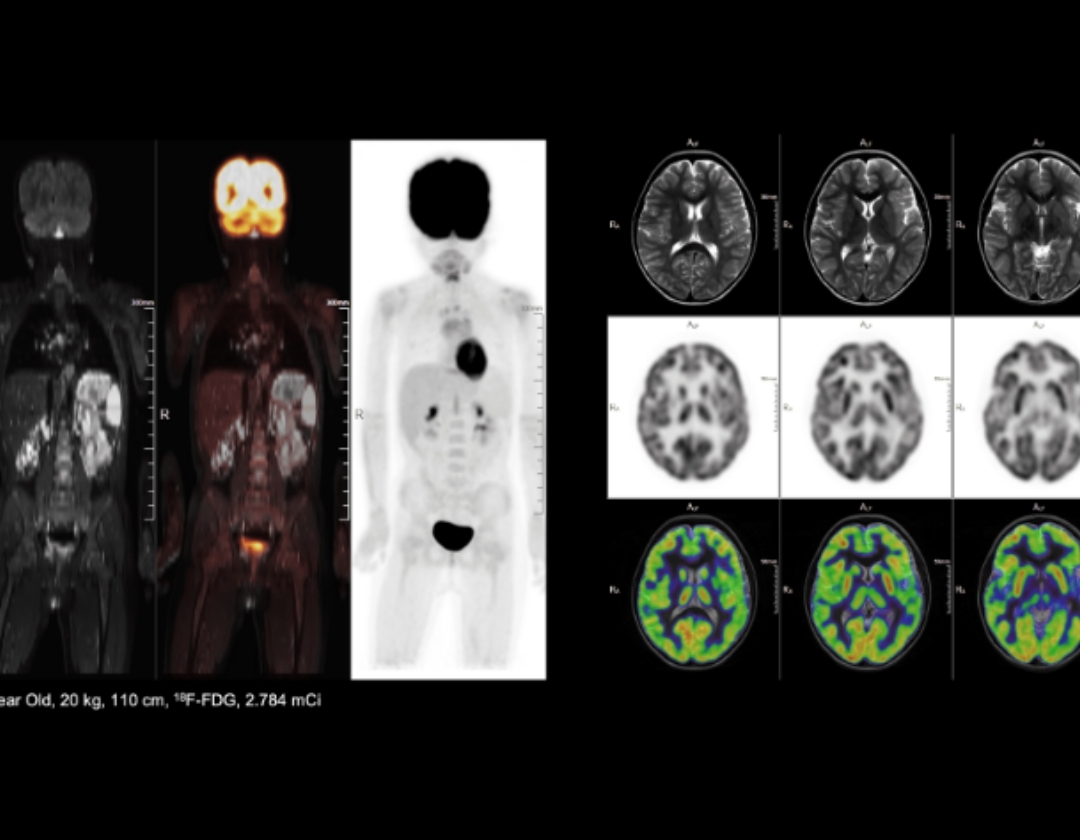

9 min high resolution whole-body PET/MR exam with low radiation dose